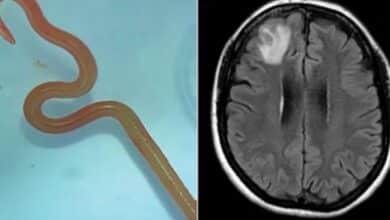

دودة حية بطول 18 سم تستقر في دماغ رجل بعد ابتلاع ثعبان